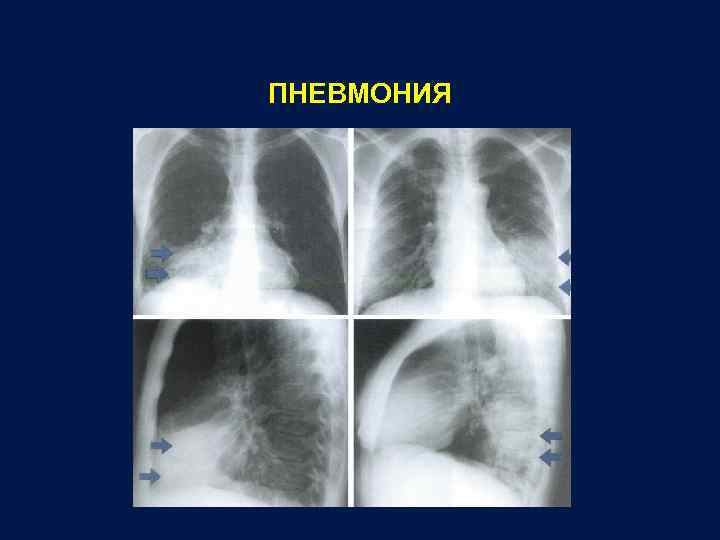

Рентгенодиагностика бронхопневмонии: Советы и примеры

Раздел: Альбом открытий